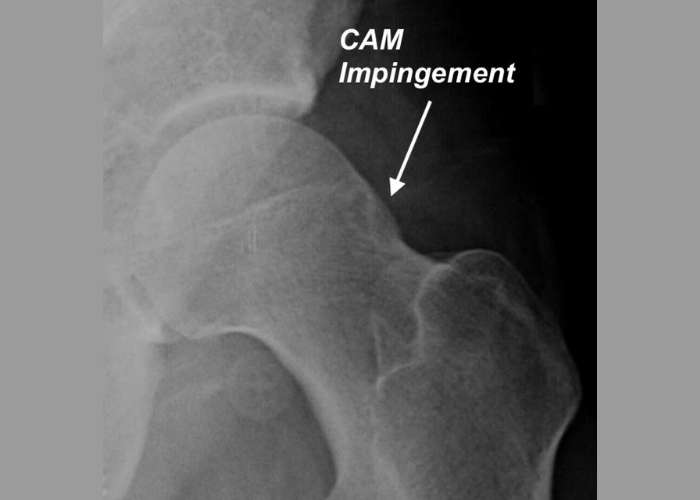

• CAM Hip Impingement, Cam Deformity in the Hip